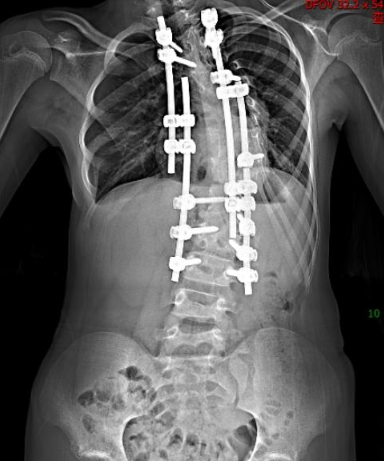

2025 年,可可年满 12 岁,胸腔、胸廓已基本发育成熟,周治国团队决定对最严重的顶椎「动手」,他们利用 3D 打印技术,1:1 还原了畸形的脊柱,并制定了截骨矫正的手术方案。

整场手术进行了 10 个多小时,周治国团队避开脊柱周围的神经和血管,对可可畸形弯曲最严重且最突出的顶椎进行截骨、重整、固定。手术结束时,可可脊柱的侧弯度数从 72 度改善到 30 度,她可像正常人一样生活。

术后第一次下地,可可惊讶感慨:「我终于可以平视这个世界了!」她说,从前身子扭着,总要费力仰头,可即便是这样,她的世界始终是歪斜的。

2 月 2 日,可可到武汉儿童医院复诊,她的双肩基本平整,身形也和普通孩子无异。「这十年,太不容易了。」看着女儿的蜕变,爸爸百感交集。